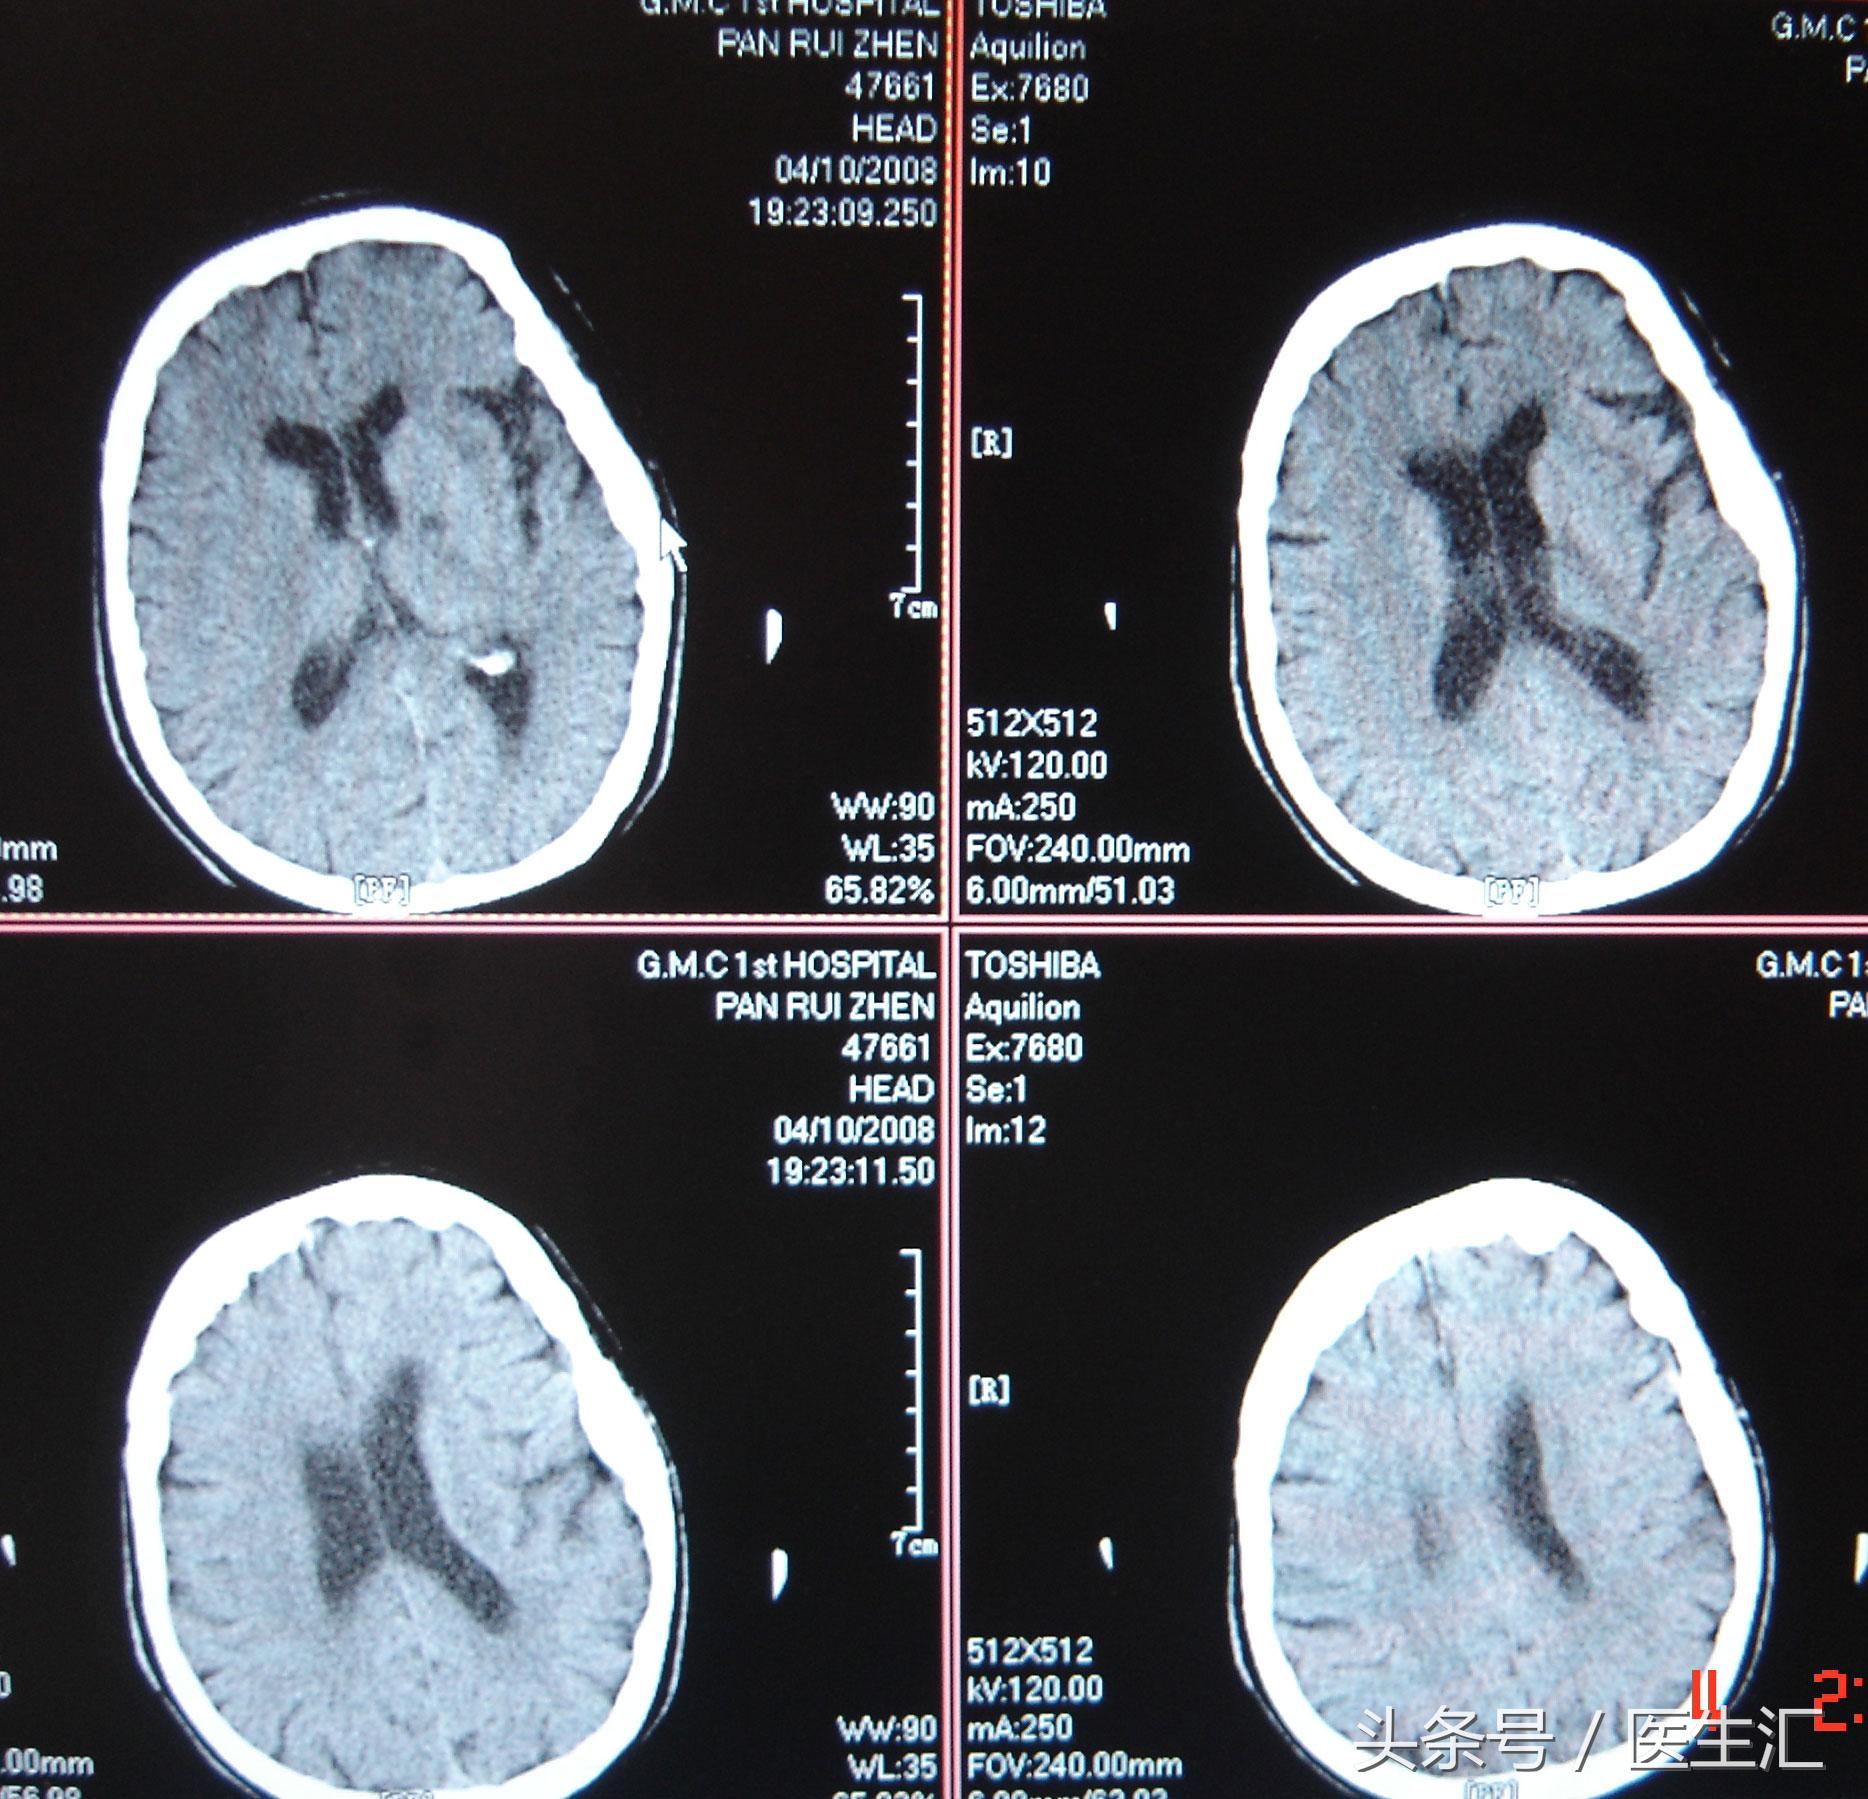

溶栓前头颅CT(见图1)

专家判读:左侧内囊区可见低密度影。两侧大脑半球及岛叶未见明显水肿低密度或者脑出血的高信号。